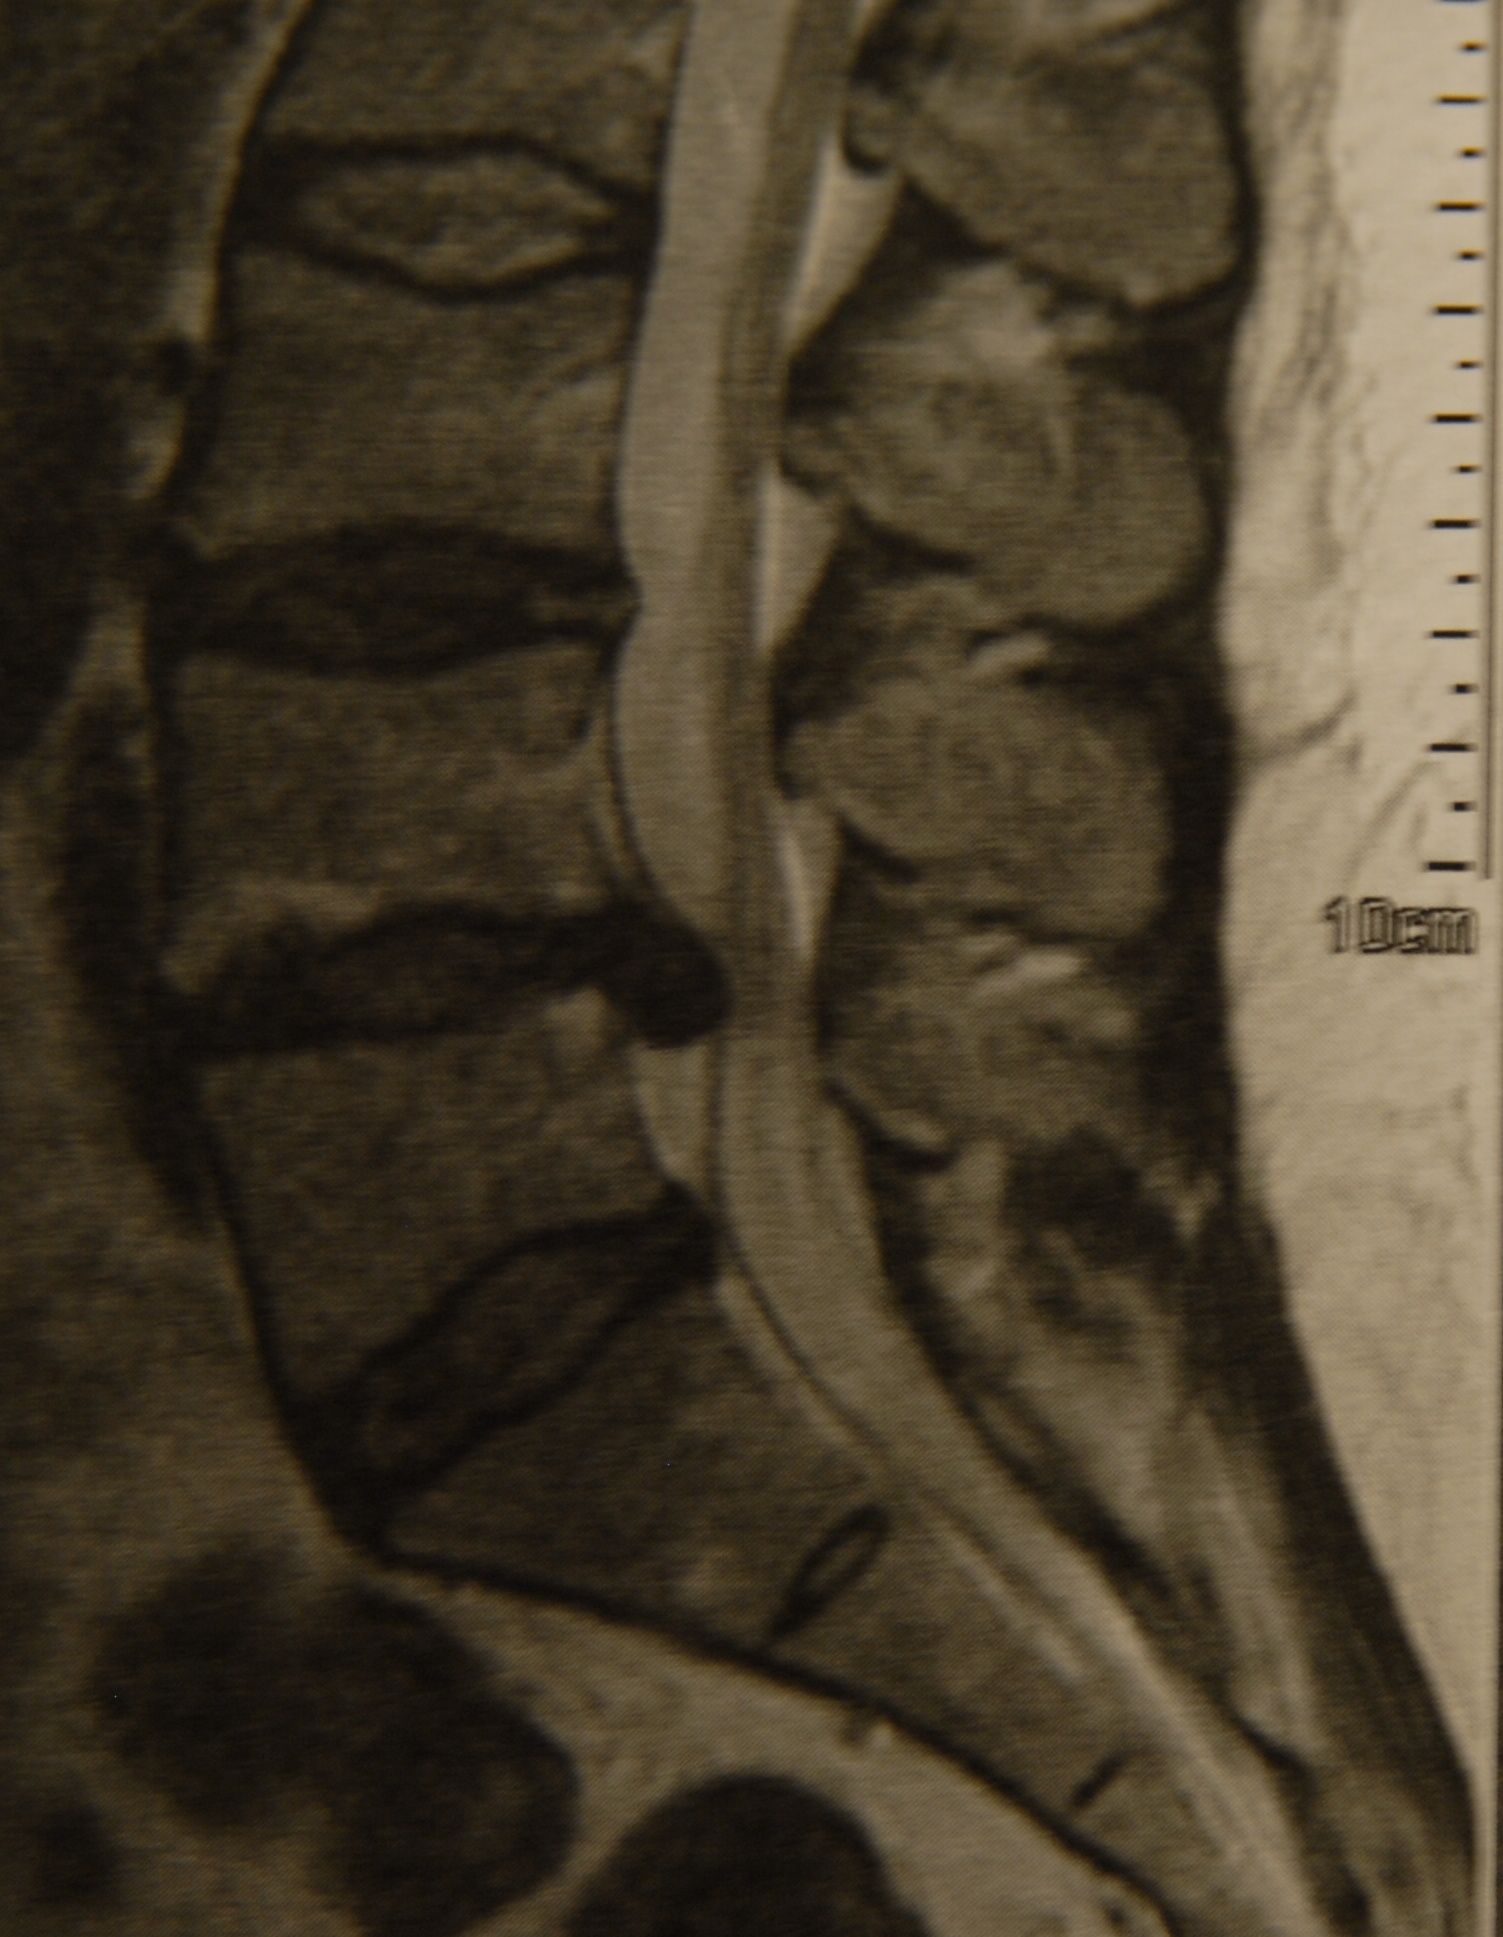

Aneurysma Hirntumor Bandscheibenvorfall

Aufgabe der Neurochirurgie ist die operative Behandlung der somatischen Erkrankungen des Zentralnervensystems und seiner Hüllen. Von Neurochirurgen werden Operationen an Gehirn, Rückenmark, peripheren Nerven sowie Schädel und Wirbelsäule durchgeführt. Solche Eingriffe sind unter anderem erforderlich bei allen Arten von Tumorerkrankungen, Unfallfolgen oder angeborenen Fehlbildungen von Gehirn und Rückenmark. Auch entzündliche Erkrankungen des Zentralnervensystems und spontan auftretende Blutungen infolge von Gefäßmissbildungen (Aneurysmen, Angiome) oder Schlaganfällen gehören zum Aufgabengebiet der Neurochirurgie. Ein weiterer Schwerpunkt ist die Behandlung degenerativer und traumatischer Wirbelsäulenprozesse, hier in erster Linie die Operation von Bandscheibenvorfällen sowie die operative Versorgung von Verletzungen der Wirbelsäule und des Rückenmarks. Nicht zuletzt werden auch Schmerzpatienten (z. B. bei Tumorerkrankungen, Trigeminusneuralgie, usw.) behandelt.